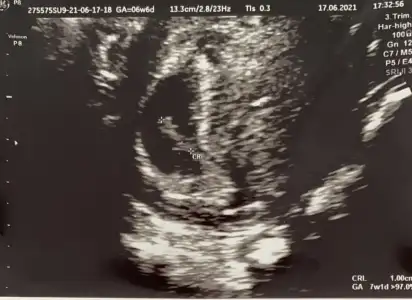

7 haftalık Karından acaba cinsiyeti ne bu teoriye gör e

Eklentiler

• 194B634C-44DA-408E-8587-9F3E5CF76A95.webp

194B634C-44DA-408E-8587-9F3E5CF76A95.webp

30,4 KB · Görüntüleme: 51